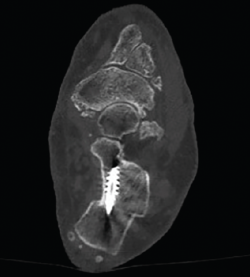

Una vez comprobado el suficiente desplazamiento en la proyección axial del calcáneo, se fija la osteotomía con 2 agujas de Kirschner sobre las que se introducirán 2 tornillos canulados de un tamaño de entre 5,5 y 7 mm, y se verifica su correcta colocación en la visión lateral y axial fluoroscópica (Figura 9).

Figura 9. Imágenes fluoroscópicas de fijación de la osteotomía con agujas de Kirschner y tornillos canulados en anteroposterior y axial del calcáneo.

Figura 11. Detalle de la osteotomía en la tomografía computarizada a los 3 meses.